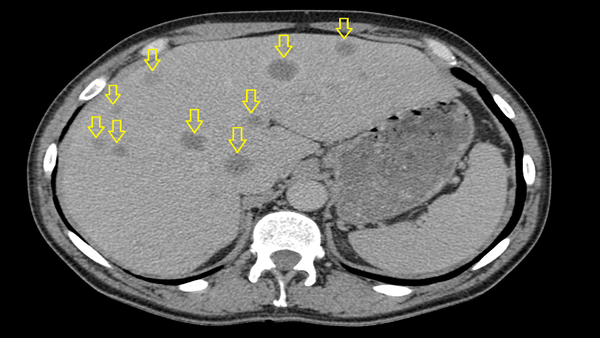

Самый критичный параметр, указывающий на наличие отдаленных метастазов — вторичных очагов опухоли в других органах (например, в печени, легких, костях).

- M1 — обнаружены отдаленные метастазы. Их наличие всегда указывает на самую тяжелую, IV стадию заболевания.

На снимке компьютерной томографии органов брюшной полости стрелками показаны множественные метастазы в печень (M1). Фото с сайта lechimkozhy.ru.